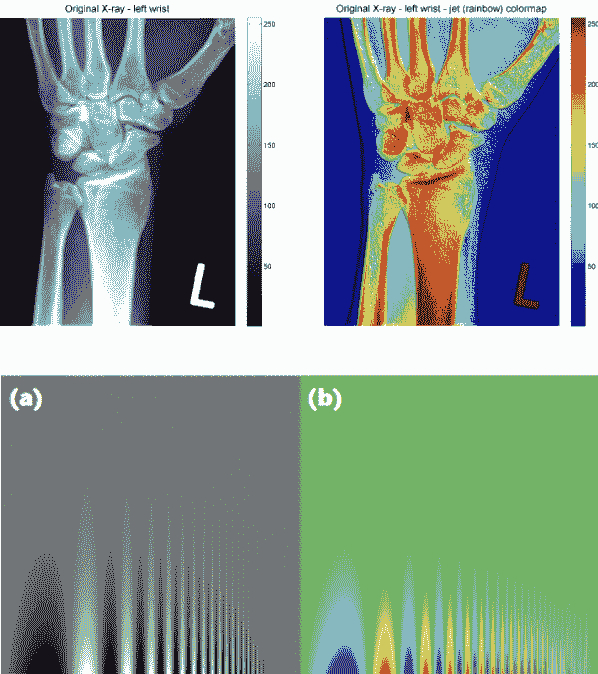

jet 色图因为不是感知均匀而臭名昭著。虽然它看起来比 viridis 更生动,但是激烈的颜色很差地编码了数值数据。为了理解原因,让我们分析以下图像。

左侧的图表比较了各种色图如何表示从高到低强度的像素数据。这些包括 jet 色图(a 行)和灰度(b 行)。注意灰度图像在平滑过渡像素数据方面做得最好。jet 色图在这方面是最差的 - a 行的四幅图像看起来像是一团独立的颜色。

这种差异在左侧标有(a)和(b)的图像中也是明显的。灰度图像更擅长保留垂直线条中的细节。此外,X 射线扫描中更偏好灰度图像,因为它更加中性。jet 色图中深红色的强度令人恐惧,并且表明出现了问题。

为什么 jet 色图要糟糕得多?答案在于它的颜色组合对人眼的感知。